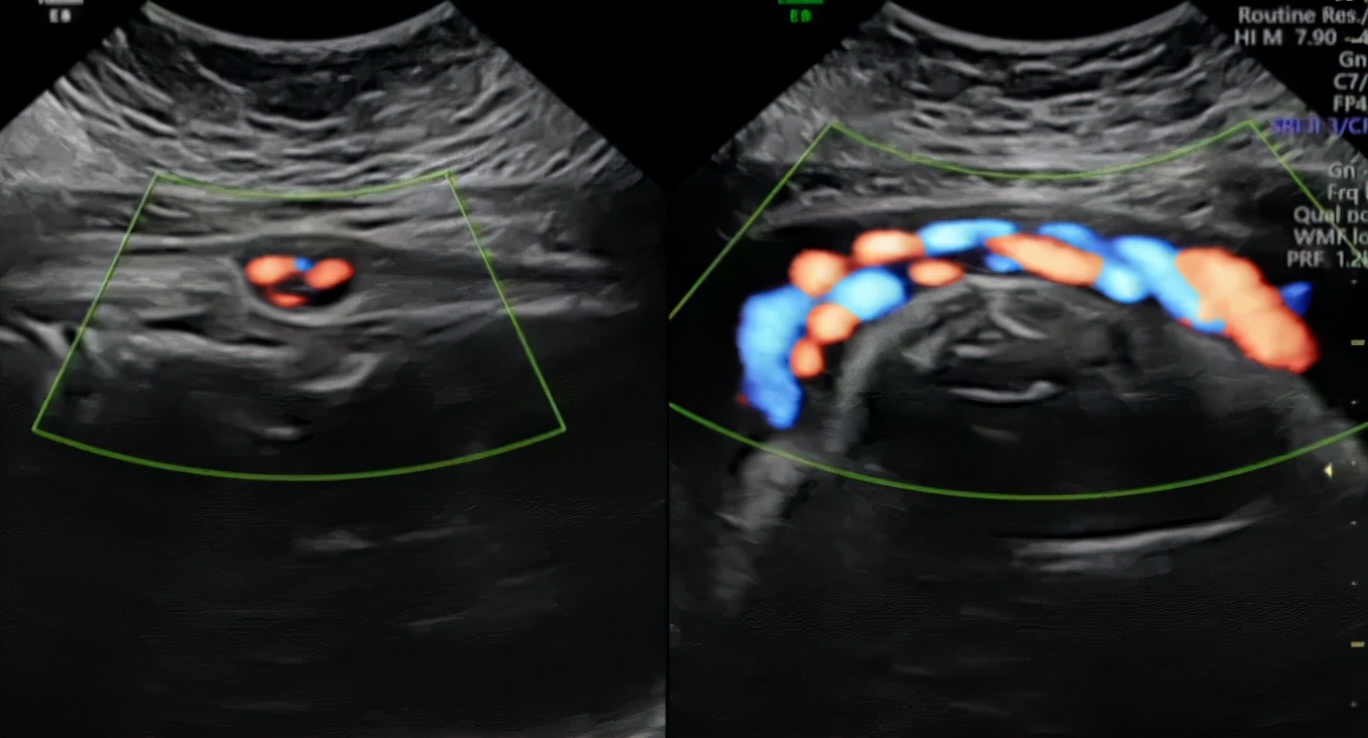

胎儿脐带是连接胎儿与胎盘的条索状组织,脐带表面有羊膜覆盖,内有一条脐静脉和两条脐动脉,脐血管周围有胶带胶质,有保护脐血管的作用。脐带是母体与胎儿气体交换、营养物质供应和代谢产物排出的重要通道。整个孕期中,脐带长度与胎儿长度基本相同,足月胎儿脐带长约40—60CM。胎儿脐带绕颈只属于“脐带缠绕”范畴中的较为常见的一种,其他还可包括绕身、绕足、绕手及绕胸腹部等多个部位。

一般情况下有脐带绕颈的宝宝的脐带通常会比较长,活动度较好。在脐带长度足够的基础上,如果宝宝的活动度比较大,那么脐带就可能随着宝宝的活动度而缠绕在颈部,有时候又会随着活动度的增大而绕出来,过段时间也有可能重新再绕上。若孕妈妈的羊水量过多,胎儿可活动的空间比较大,就比较容易发生脐带的缠绕。如脐带缠绕的周数过多、太紧,可致胎儿缺氧,呼吸窘迫。